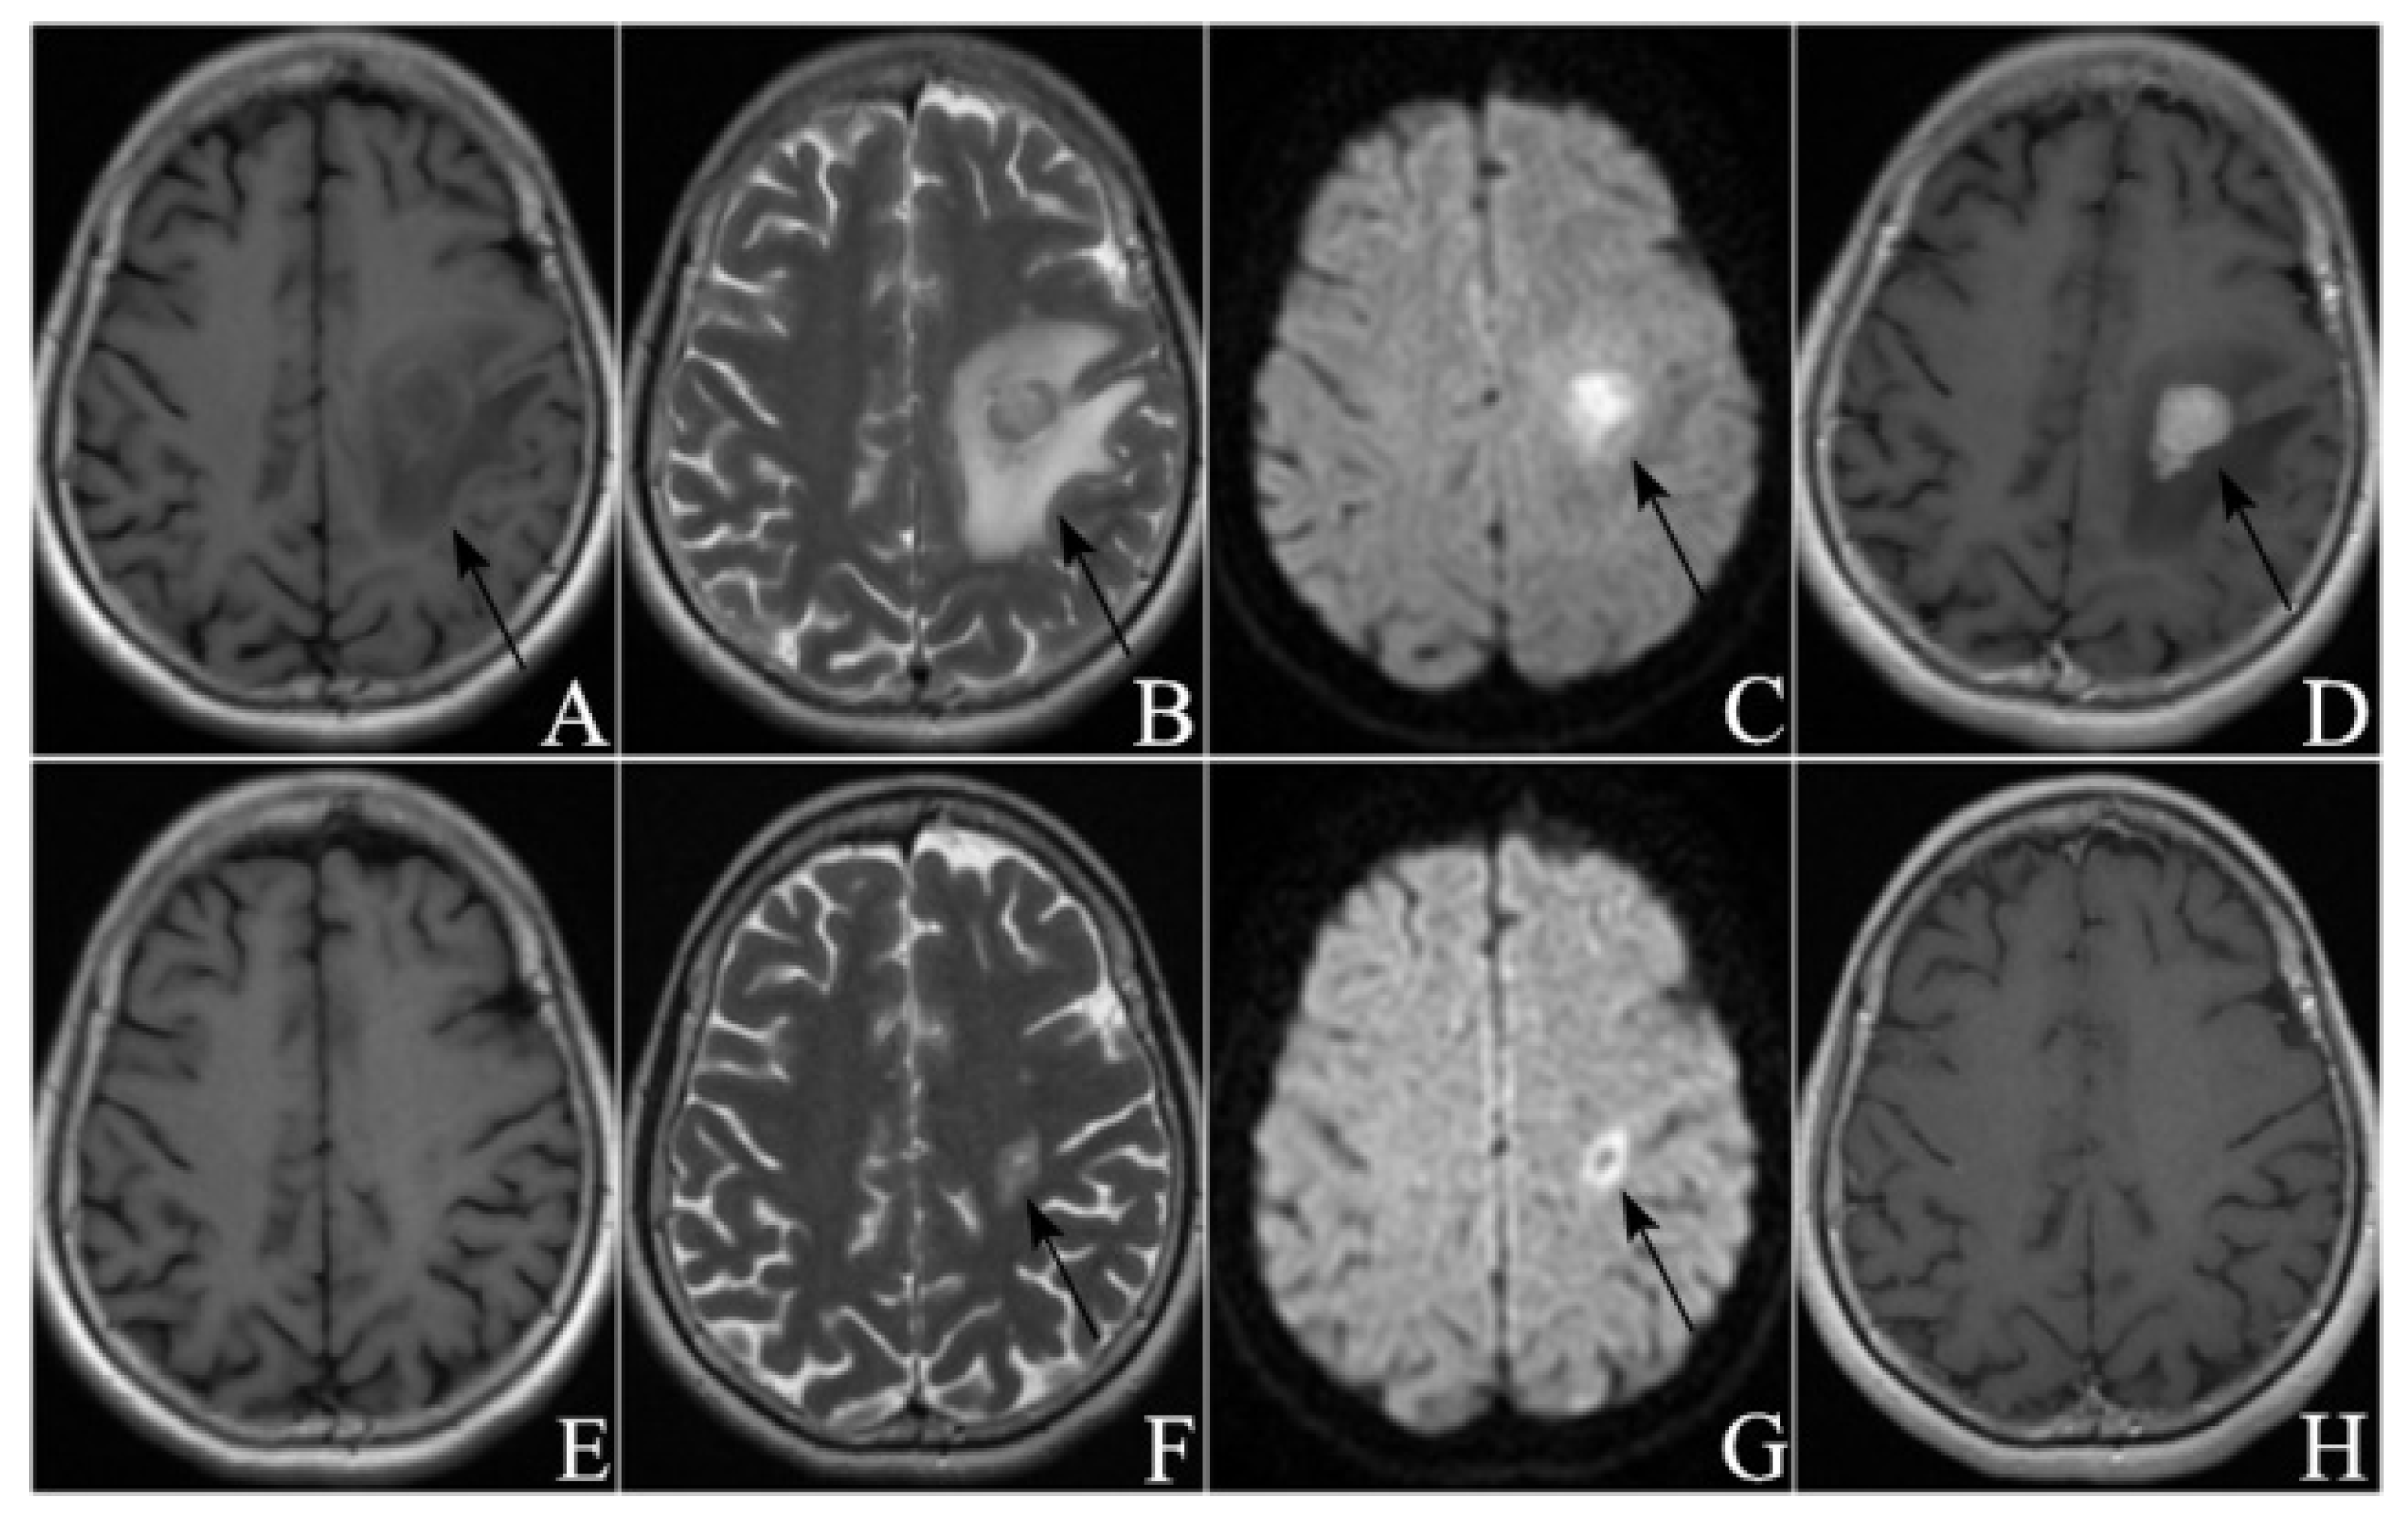

3.2. Radiological Manifestations